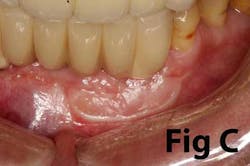

There is an abundance of literature showing increased gingival inflammation around natural dentition (exacerbated when a fixed restoration is present) when there is less than 2 mm AG. (Figs. 8, 9: post grafting) There is an abundance of literature showing increased incidence of peri-implant mucositis when there is inadequate attached tissue — a weaker connective tissue adhesion and lack of Sharpey’s fibers make the peri-implant tissue even more susceptible to bacterial challenge. (1-6, 8, 10) And as periodontitis is always preceded by gingivitis, peri-implantitis will be preceded by peri-implant mucositis. If we can decrease the incidence of peri-implant mucositis by providing a better and more resilient tissue phenotype, we can lower the incidence of peri-implantitis.The FGG procedure is indicated in cases of implant therapy where this is less than 2 mm of attached tissue present. Sometimes, a FGG is preferred over CTG because: (1) the FGG results in greater gain of attached tissue, (2) the FGG alleviates frenum/muscular pull whereas the connective tissue may increase muscular tension after the flap is coronally advanced, and (3) creeping attachment is often a positive byproduct of the FGG procedure.

Case No. 1

Case No. 2